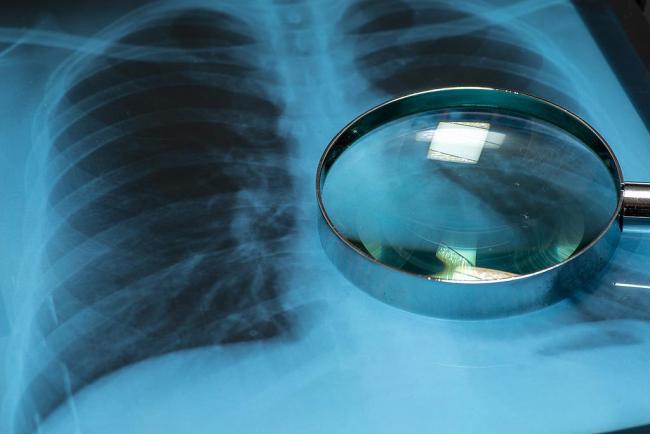

目前研究证据较为充分且共识度较高的推荐筛查的癌症主要包括肺癌、乳腺癌、宫颈癌和结直肠癌。